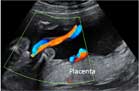

La ecografía Doppler estudia el flujo sanguíneo dentro de los vasos. En este caso, se analiza la circulación sanguínea en el cordón umbilical, es decir, como llega la sangre oxigenada de la placenta al feto y el camino contrario, la sangre poco oxigenada del feto a la placenta.